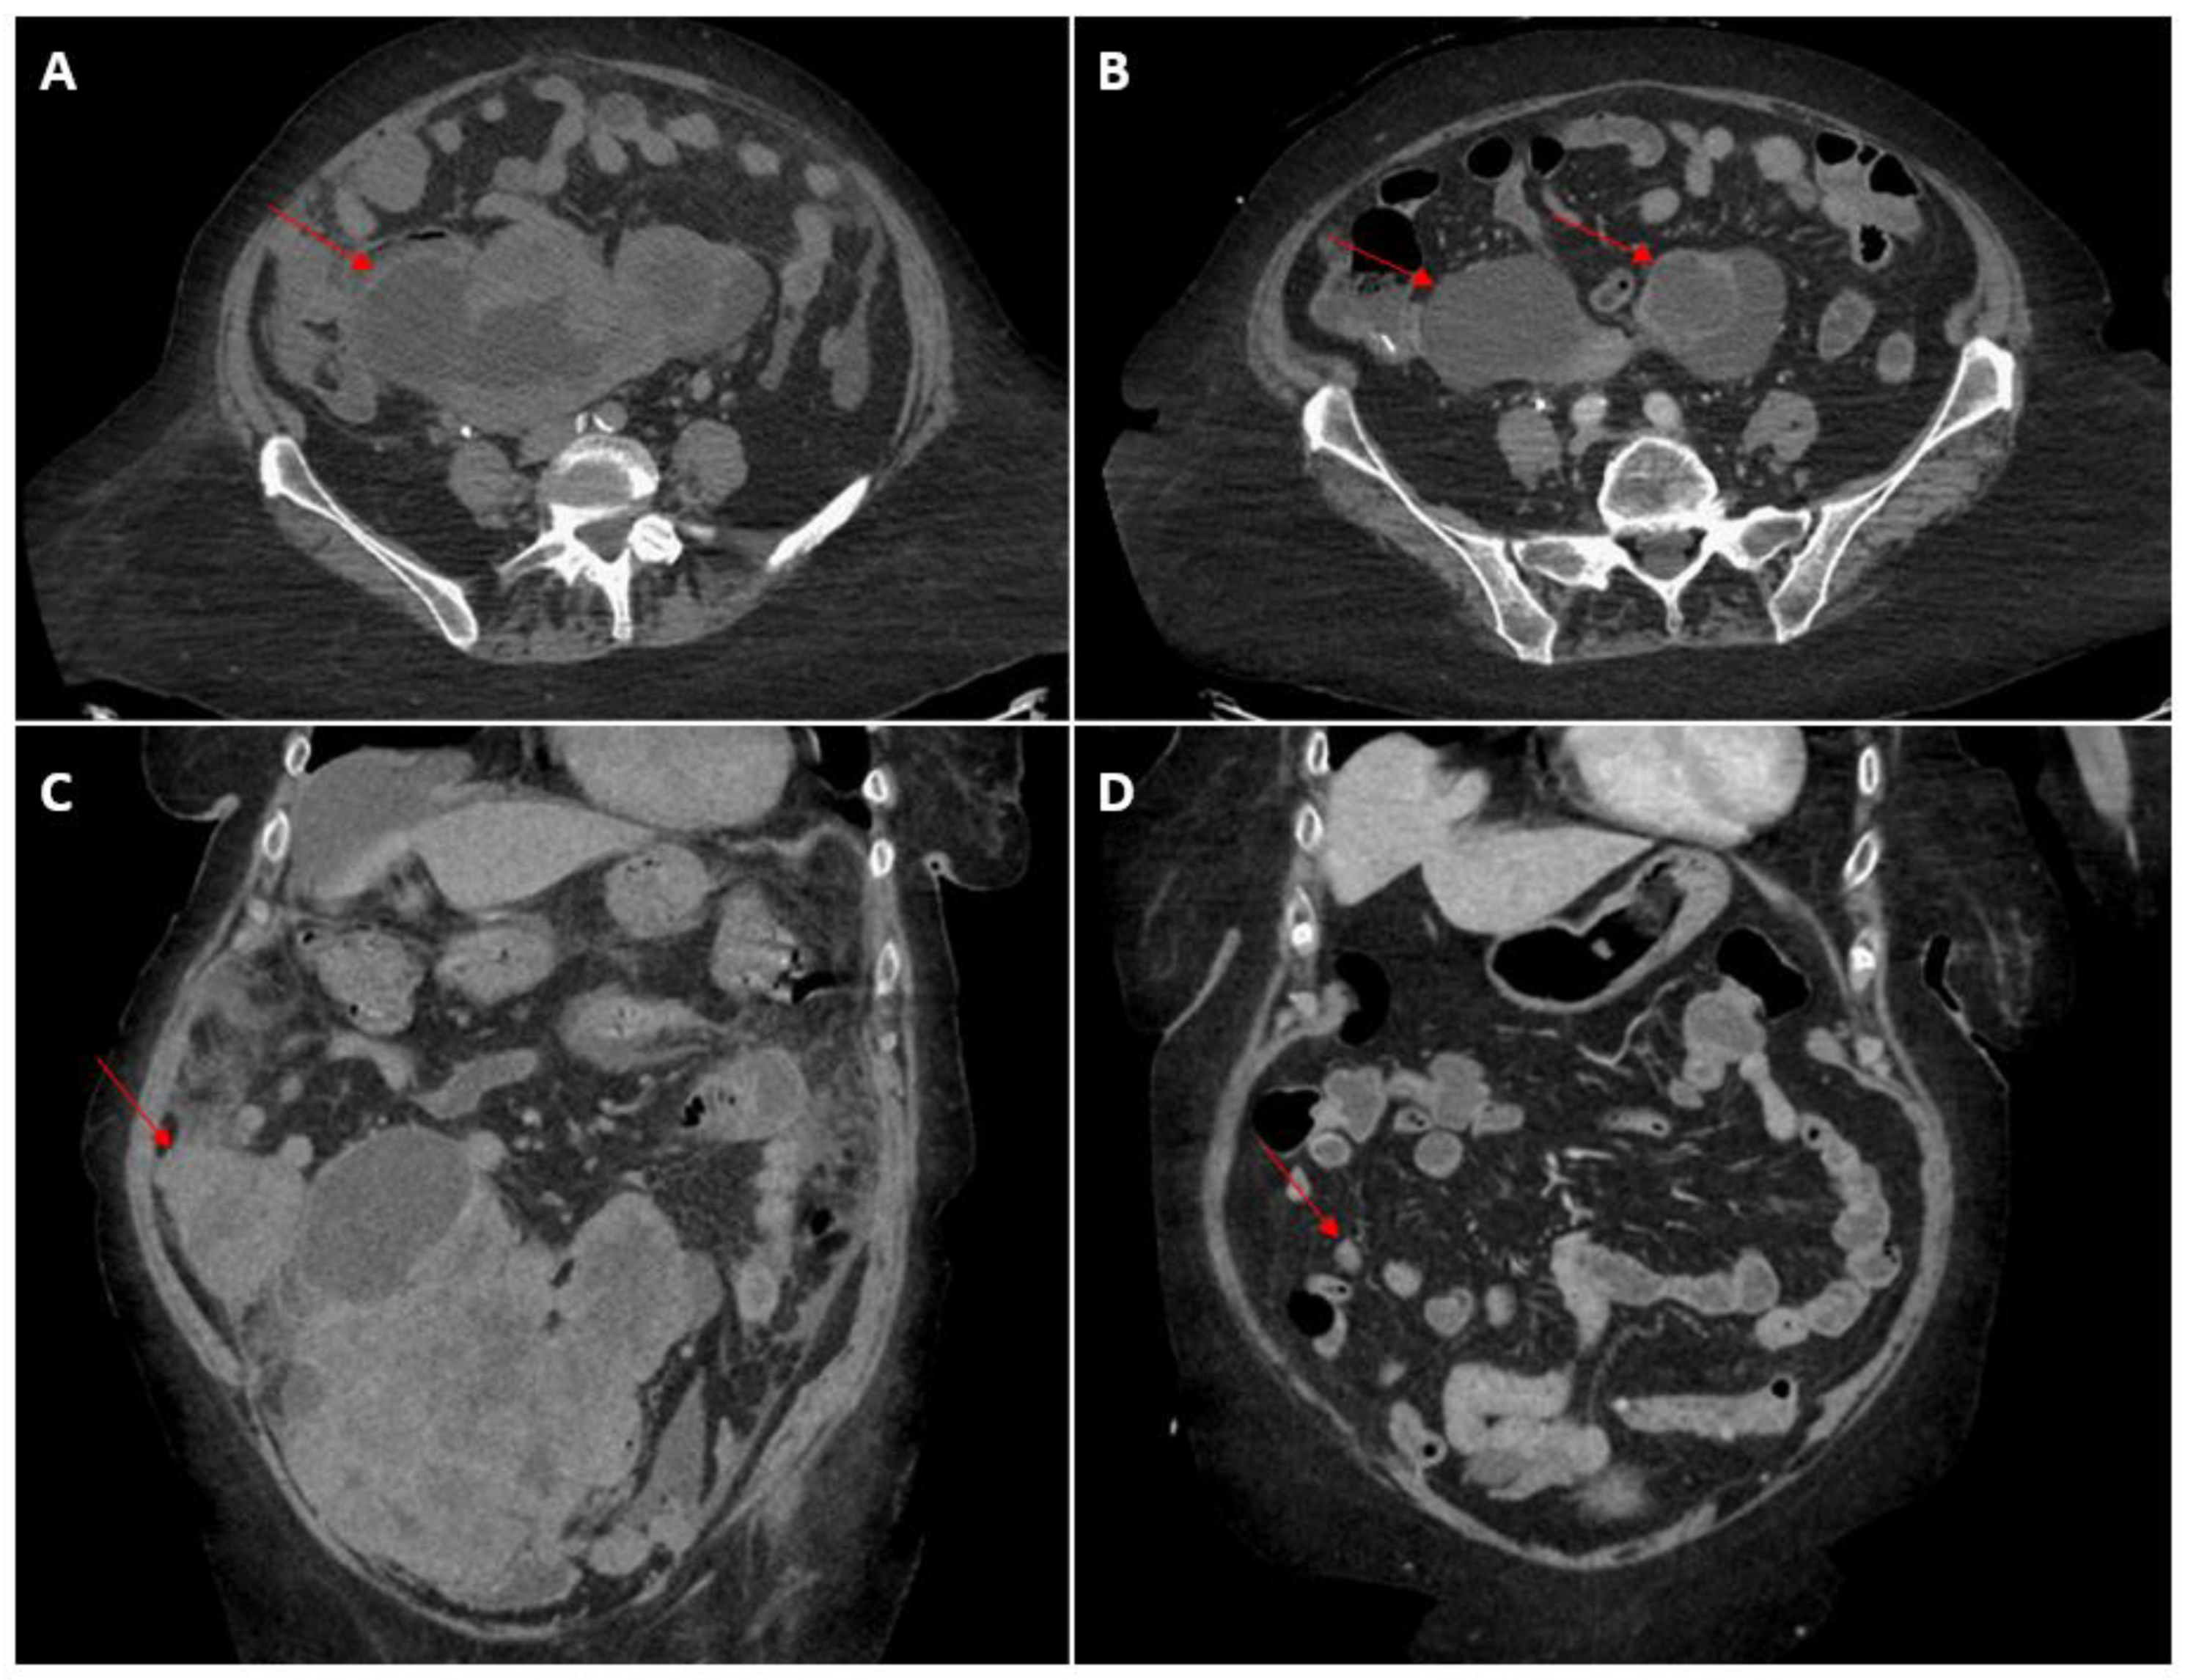

2. Case Presentation